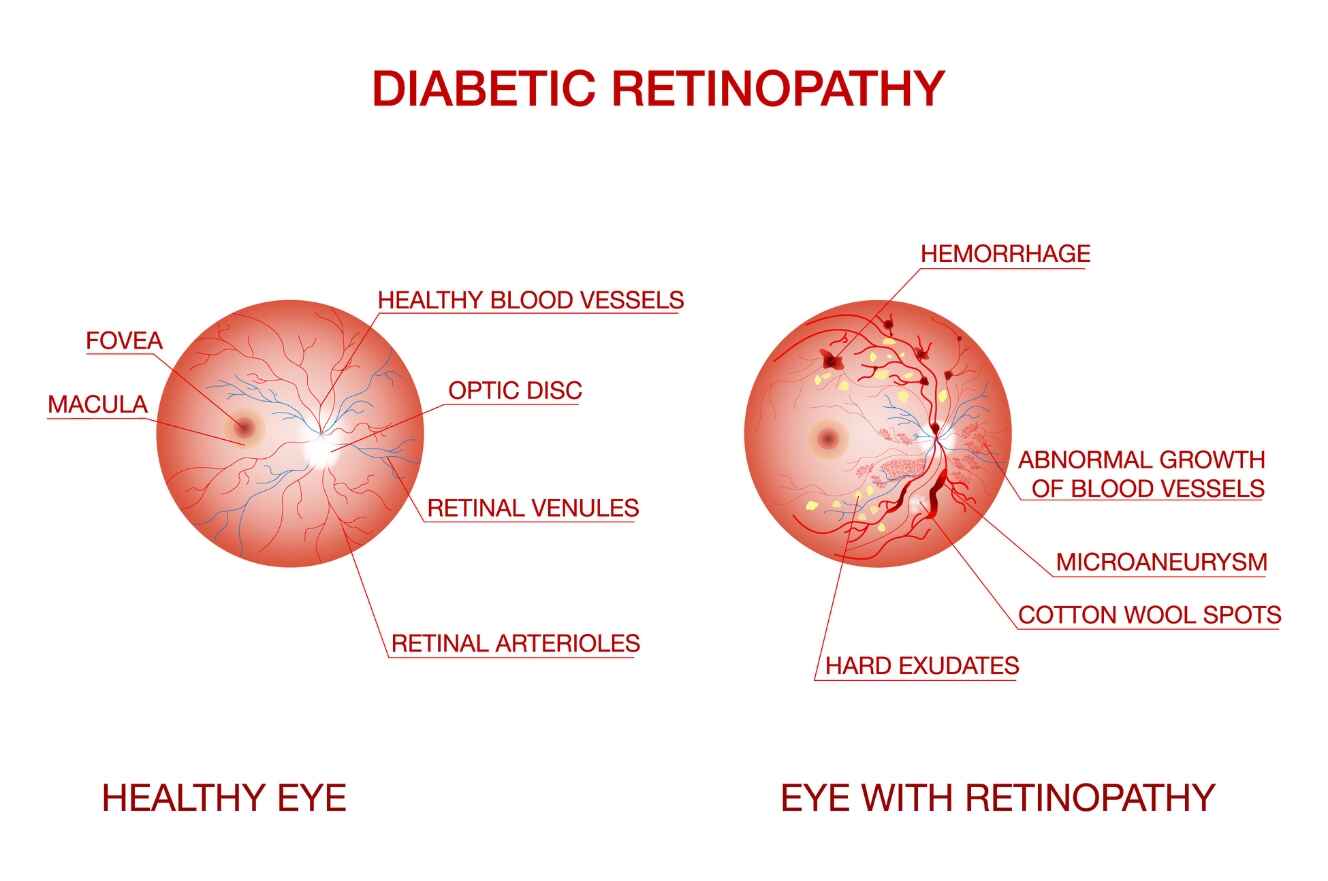

Diabetic Retinopathy